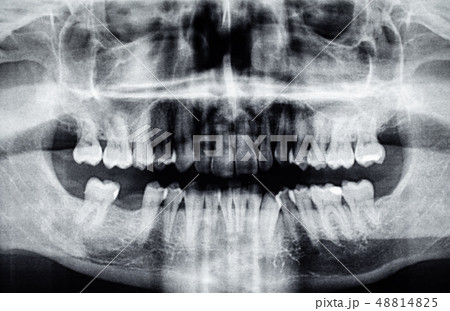

デンタルエックス線写真 SOLIO XZⅡ / SOLIO XZⅡMAXIM | X線撮影装置 | タカラの詳細情報

SOLIO XZⅡ / SOLIO XZⅡMAXIM | X線撮影装置 | タカラ。◇デジタルCMOSセンサー EzSensor Soft サイズ2.0 (25.9×35.9mm。歯科用X線装置選定ガイド - 朝日レントゲン工業株式会社。デンタルエックス線写真斉田 寛之クインテッセンス出版書き込み等もなく比較的綺麗な方かと思います。歯科用X線撮影 - 米沢市立病院。